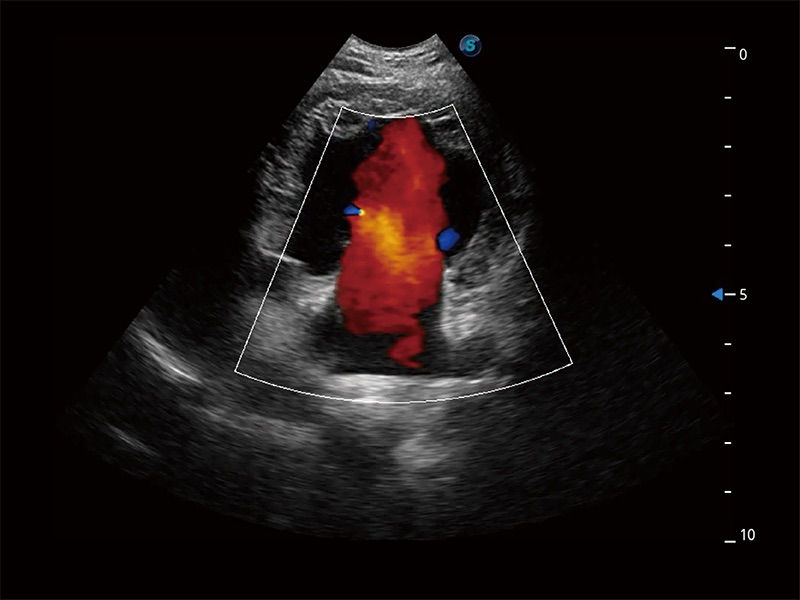

在传统二维血流成像的基础上,呈现血流的立体感,具有动感的生命力之美。即便是微小的血管也能轻松应对,提高了血流的视觉敏感性。

非线性融合造影成像充分利用谐波和基波信号,为难以观察的血流进行增强显像。可用于线阵、凸阵、微凸阵、相控阵探头。